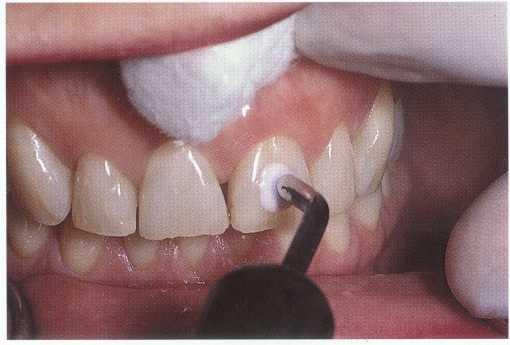

THERMAL TESTING. Thermal sensitivity is a common chief complaint in pulp pathosis. Testing with hot and cold identifies the tooth and is instrumental in determining whether the pulp is normal or inflamed. Cold testing is usually performed first. Carbon diox-

ide, or C02 (Figures 1-2 and 1-3), ethyl chloride, dichlorodifluoromethane (Figure 1-4), and ice sticks (Figure 1-5) are frequently used to apply cold to teeth. These tests have been shown to be safe and do not cause damage to the pulp8,9 or enamel.10 Patients should be advised of the testing method and expected sensations. The testing should begin on a normal "control" tooth (usually of the same tooth group or type) to educate the patient regarding what to expect from the test, determine whether the test will provoke a response (validating the use of the

FIGURE 1-3 C02 snow application to tooth #9, which is non-

FIGURE 1-9 Electric pulp testing can be used to establish pulp vitality or confirm non responsiveness. In this case the failure of tooth #9 to respond confirms the results obtained with thermal testing.